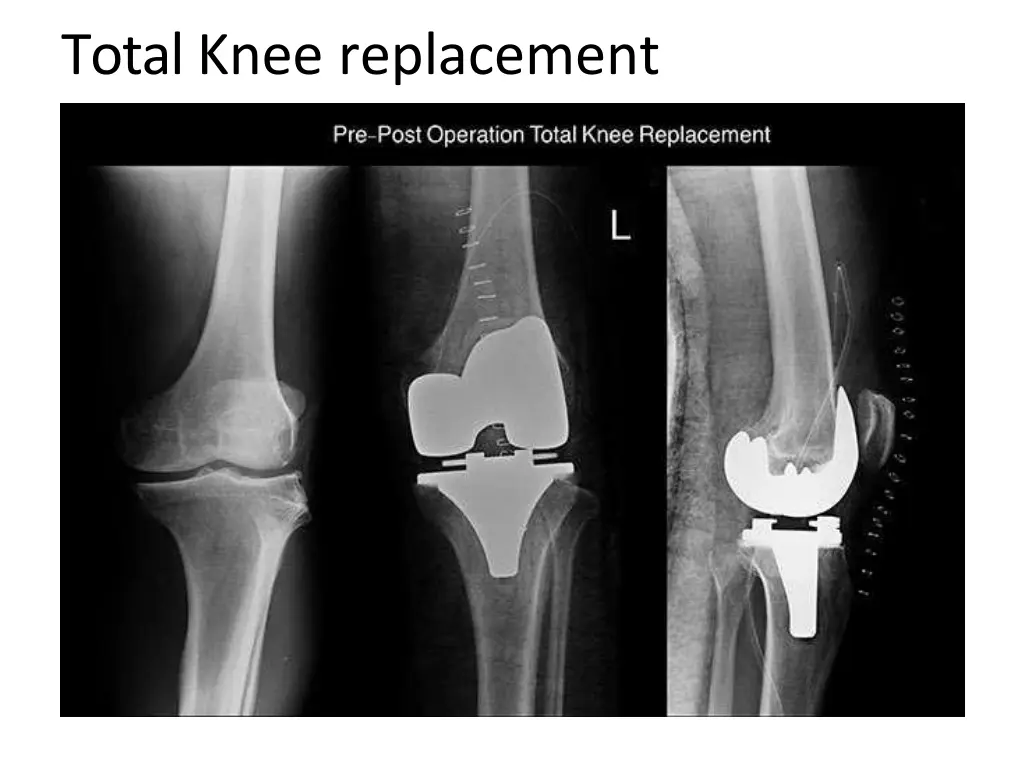

11. Total Knee replacement

Uploaded on Apr 22, 2025 | 0 Views